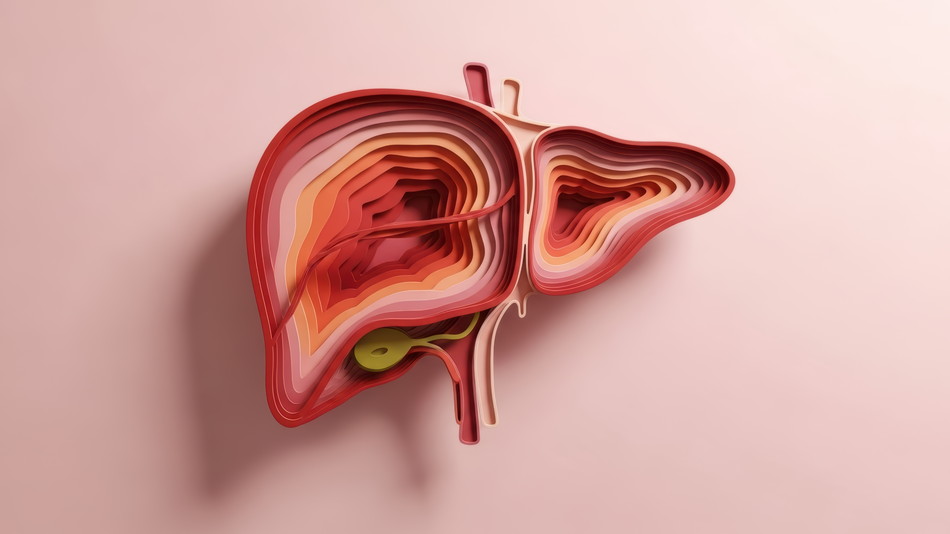

命の楽団を操るマエストロ 体の中には、音も立てず、主張もせず、それでも全体を支配している存在があり...